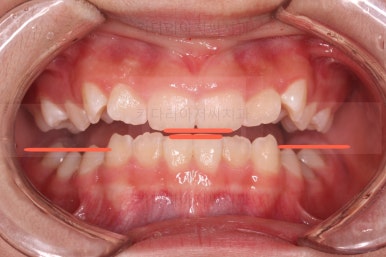

오른쪽 상단 사진을 보시면 어금니의 높이와 앞니의 높이가 차이가 많이 납니다.

앞니가 솟구쳐 있는 양상인데요.

그 이유 때문에 어금니로 다물었을 때의 위아래 앞니가 많이 겹쳐서 아래 앞니가 아예 보이지 않는 상황이었어요.

이를 "과개교합"이라고 표현합니다.

앞니 각도가 매우 좋아졌고요.(옥니 개선) 위아래 앞니가 덮는 정도도 개선이 되었어요.(과개교합, 딥바이트)